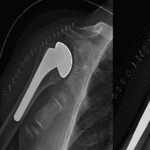

X-rays

X-rays provide images of dense structures, such as bones. Your doctor will order X-rays of your elbow to help diagnosis your fracture. Depending on your symptoms, the doctor may also order X-rays of your upper arm, forearm, shoulder, wrist, and/or hand to determine whether you have other injuries.

This X-ray taken from the side shows an olecranon fracture in which the pieces of bone have moved out of place (displaced).Reproduced from Konda SR: Fractures around the elbow, in Egol KA, Gardner MJ, eds: Let’s Discuss Management of Common Fractures. Rosemont, IL, American Academy of Orthopaedic Surgeons, 2016, pp. 17-30.